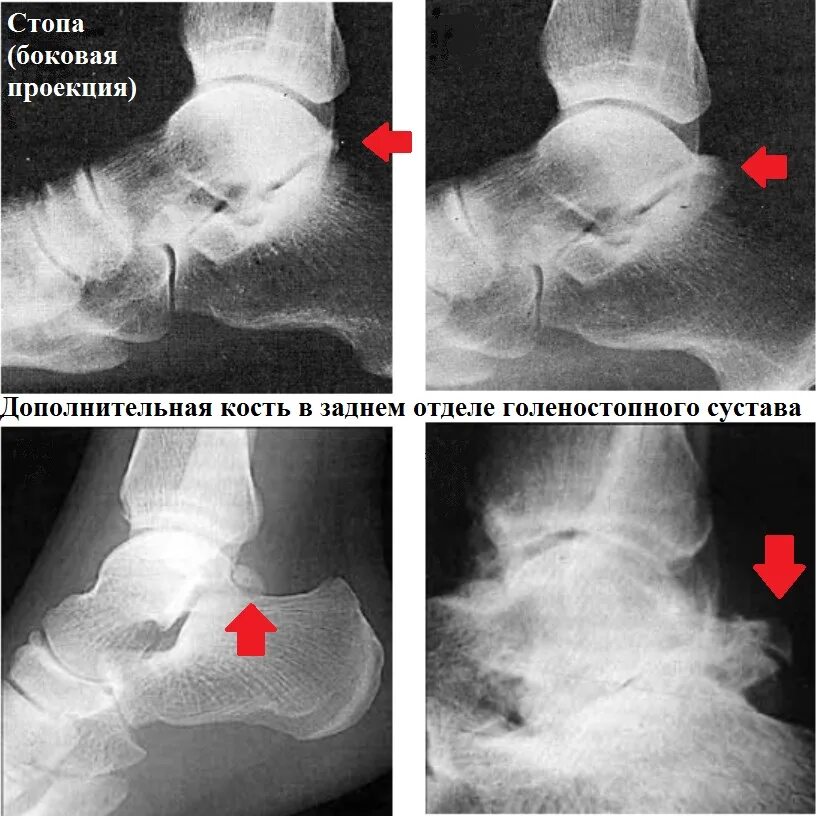

Движения в голеностопном суставе